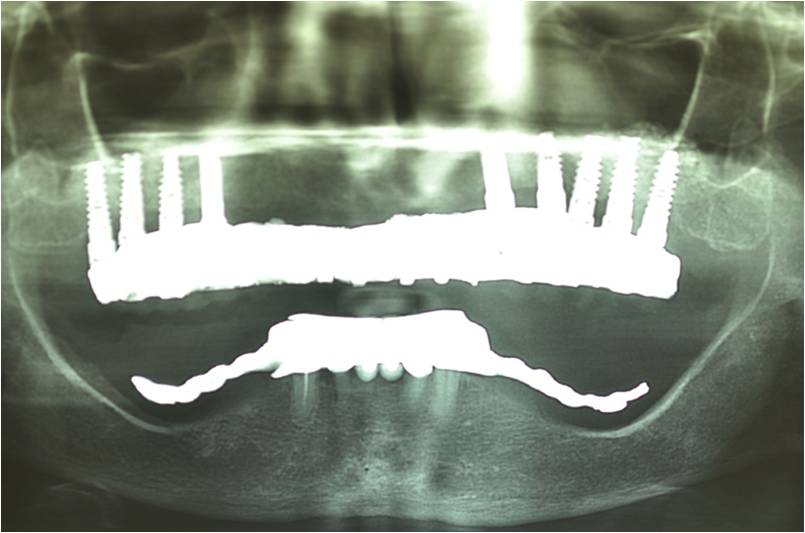

עקב חוסר בעצם ואי רצון מצד המטופל לעבור הרמות סינוס בוצע תיכנון ממוחשב של מיקום השתלים עוד בטרם ההשתלה.

ההשתלות בוצעו דרך שבלונה שהוכנה במדפסת תלת מימד בהתאם לקובץ הממוחשב.